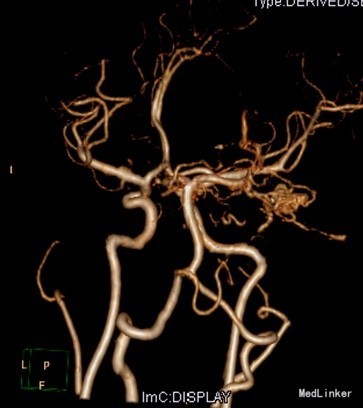

查体:昏迷,双瞳大形圆约3mm,四肢及肌力张力不合作。辅助检查:CT提示蛛网膜下腔出血,脑室铸型。头部CTA提示:广泛蛛血,脑室系统明显积血,脑实质稍肿,中线居中;右侧颞叶约侧脑室区积血内见增多、迂曲团状血管影,似主要由右大脑后动脉分支供血,考虑血管畸形可能性大。行全脑血管造影提示右侧小脑动静脉畸形,供血动脉来自右侧小脑上动脉、右侧大脑后动脉。